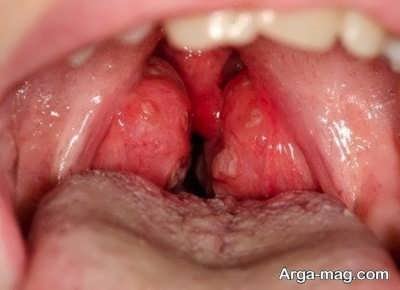

• در واقع شما به راحتی و با نگاه کردن در آینه می توانید این بیماری را تشخیص دهید و کافی است دهان خود را باز کرده و حروف آ را مرتب تکرار کنید.

• شما زمانی که این کار را انجام می دهید باعث خواهید شد تا لوزه هایی که پشت گلوی شما می باشند به راحتی دیده شوند.

• اگر این لوزه ها قرمز ملتهب بود باید بدانید که به این بیماری دچار شده اید.

• معمولا ویروس‌ها و باکتری ها منجر به ایجاد این بیماری می شوند و اگر علاوه بر التهاب روی لوزه های خود لکه های قرمز ریز را مشاهده کردید باید در نظر داشته باشید که این مورد را ویروس اپشتین ایجاد کرده است.